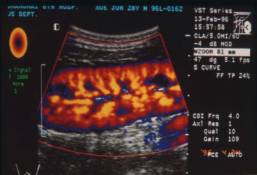

4.1 多普勒血流显像